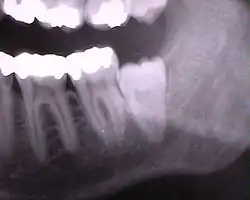

Pantomogram pacjenta z zatrzymanym dolnym lewym i stłoczonymi górnymi zębami mądrości.